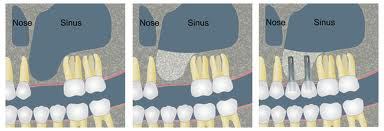

Grande rialzo di Seno Mascellare

Continua